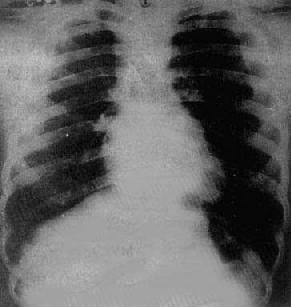

房间隔缺损

图3-2-21 房间隔缺损

右前斜位:右心室增大,肺动脉段突出,心前间隙变窄,无左心房增大后前位:心增大,呈二尖瓣型,右心房及右心室增大,肺动脉段突出,肺纹理增强左前斜位:右心房及右心室增大,左心室被增大的右心室推向后